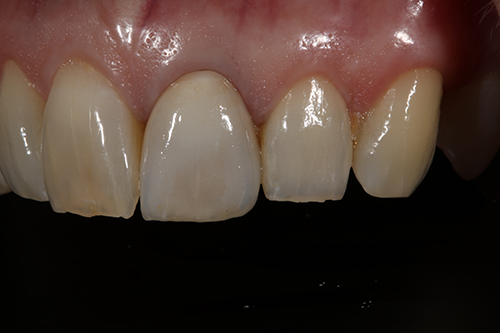

Fig. 1 Fig. 2

The comprehensive oral examination, which included radiographs, revealed nothing that would contraindicate this treatment plan (Fig. 2). In fact, the previous endodontic treatment was acceptable, and the post was well-adapted to the tooth. The risks and benefits of removing the post were discussed with an endodontist and ultimately the patient, and it was decided to leave the existing cast post and core in place. However, doing so would create prosthetic challenges, including identifying a material that offered an esthetic outcome while blocking out the dark-colored post and core. For this reason, a full-coverage crown fabricated from zirconia was recommended and accepted by the patient.